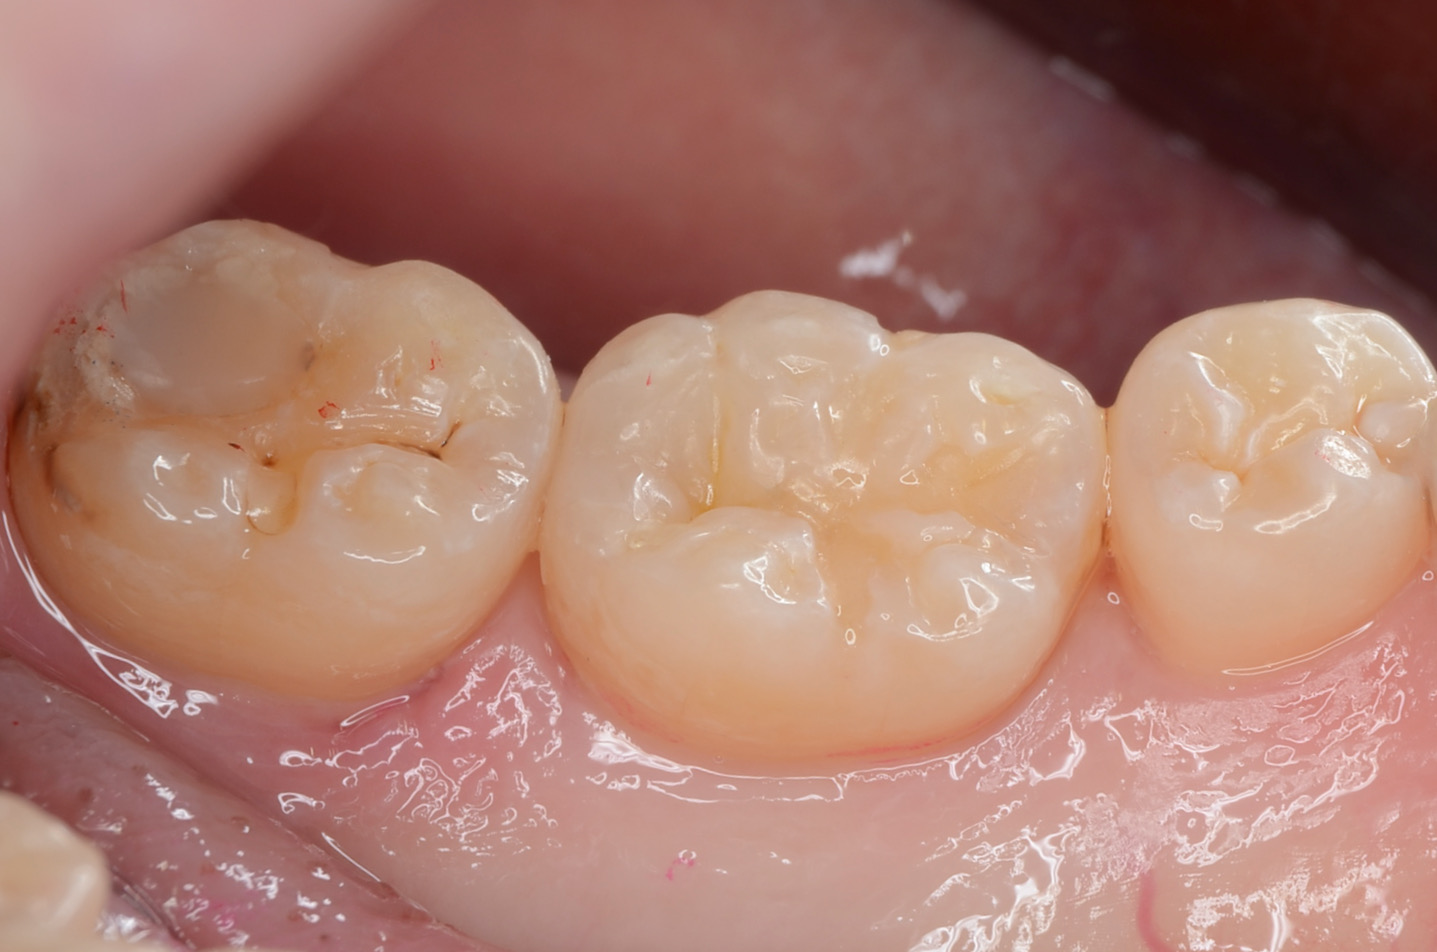

Before

After